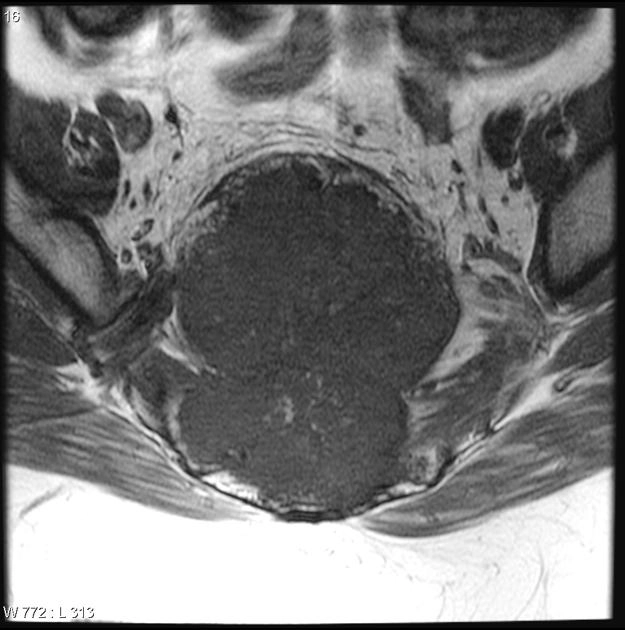

U dây sống ác tính (Sarcoma Chordoma)